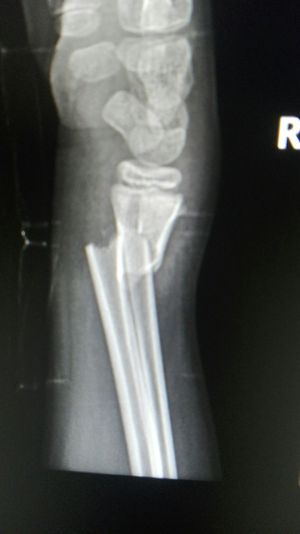

Xray

Fractures

Wrist